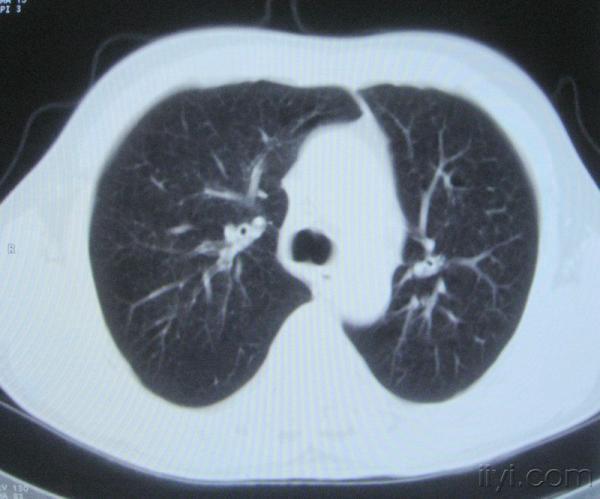

男。60岁,胸片示支气管炎治疗后复查CT。

你指那个肯定是淋巴结,中央系坏死,这很常见,特别在双侧腹股沟会经常看到。这个双侧腋窝及纵隔见多发小淋巴结征。

根据位置考虑应该是淋巴结,密度不均,是因为肿大的淋巴结中心液化坏死